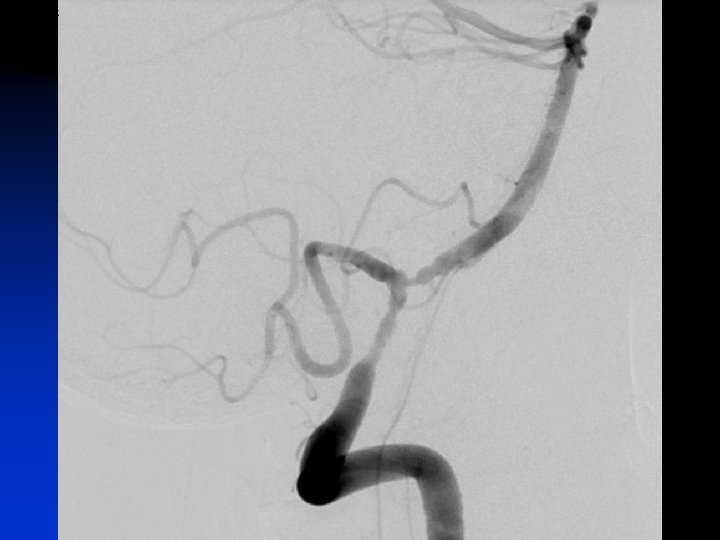

Cerebri post Cerebelli sup Basilaris Vä AICA Vä PICA Spinalis ant V 4 V 3 Vä vertebralartär

n n n Direkt postop upplevd förbättrad syn och balans Inga ytterligare anfall Uppföljande CT-angio utan restenosering